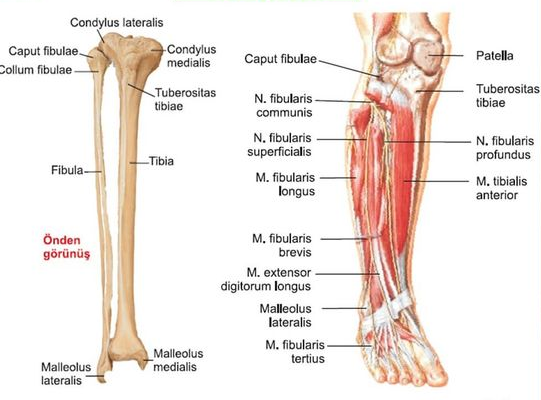

TIBIA

Femur’dan sonra iskeletin ikinci en uzun ve en ağır kemiğidir.

En büyük foramen nutricium’u olan kemiktir. Bu delikten geçen nutrisiyen arter, a. tibialis posterior’un dalıdır.

Tuberositas tibiae; gövdesinin üst bölümünde bulunan bu pürtüklü alana, m. quadriceps femoris (bacağın esas ekstensör kası)’in tendonu (lig. patellae) tutunur.

Tibia’nın alt ucunun iç tarafından aşağı doğru uzanan kaim çıkıntıya malleolus medialis denir. A. tibialis posterior un pulsasyonu, malleolus medialis’in arkasında alınır.

Bu çıkıntının arka yüzü üzerindeki sulcus malleolaris’ten, m. tibialis posterior’un tendonu geçer.

FİBULA

Kemik grefti olarak kullanılan fibula’nın ana fonksiyonu, kaslar için tutunma yeri sağlamaktır. Direk olarak vücut ağırlığının taşınmasında fonksiyonu yoktur.

Femur’la eklem yapmaz.

Caput fibulae; m. biceps femoris sonlanır.

Collum fibulae; n. fibularis (peroneus) communis ile komşudur.

Alt ucundan aşağıya uzanan çıkıntıya malleolus lateralis denir. Bu çıkıntının arkasında bulunan derin oluk yani sulcus malleolaris’ten, m. fibularis (peroneus) longus ve brevis’in tendonu geçer.

Malleolus lateralis arkasından yüzeyel olarak n. suralis ve v. saphena parva geçer.